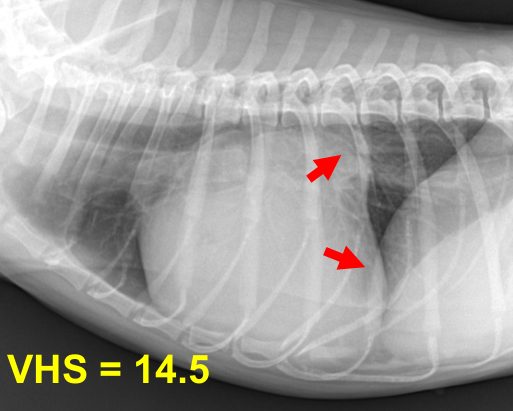

⏺️ MMVD = MVI (Mitral valve insufficiency)

Mitral valve regurgitation, degeneration도 다 같은 말.

Mitral valve (LA-LV 사이) 판막 역류 → 좌심방 혈액량 증가 → 폐정맥 혈액량 증가 → 폐정맥 비대 → 폐도 congestion → 혈액이 혈관을 따라 밖으로 흘러나오면서 폐도 물이 참 → tachypnea, 호흡 곤란, 산소 포화도 감소

1) 1, 2기 : Moderate cardiac remodeling / 3기 : Severe remodeling

| 1기 (Moderate : 좌심방귀 볼록한 정도) |

| 1) 심장 커짐 Cardiomegaly, left auricle 확장, 전허리/후허리 소실 : 심장이 부풀면서 일자형이 됨. + Sternal contact : 심장과 sternum 거리 좁아짐 2) 기관에 영향 좌심방 비대 ⇒ 기관 상승, carina를 눌러서 기침 유발 (주로 밤에 기침) : tracheal elevation, bronchial collapse, noctural cough |